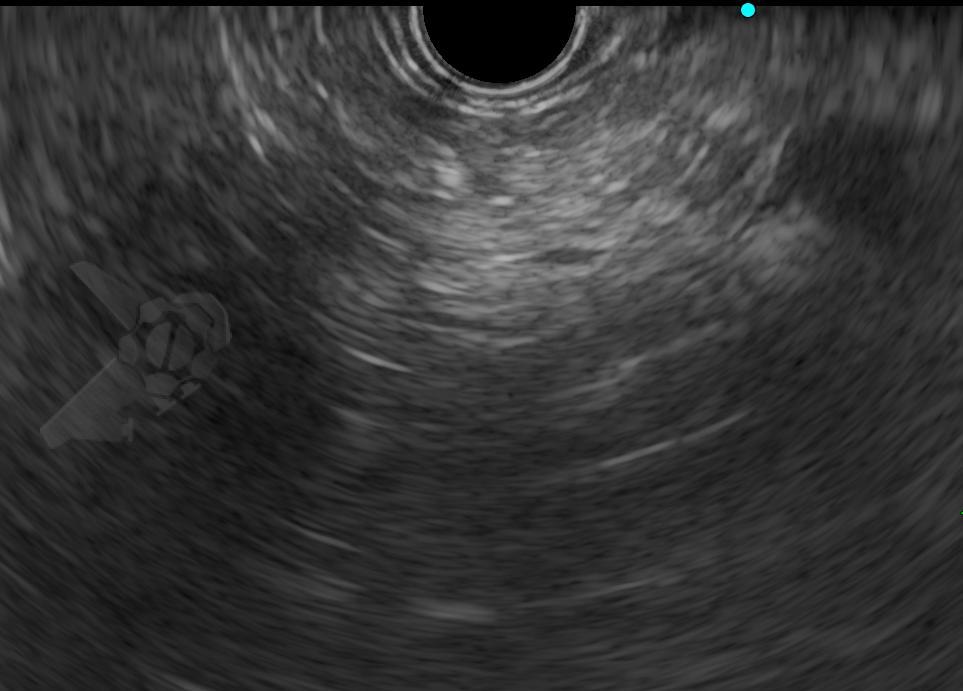

El diagnóstico se realiza preferiblemente mediante tomografía computarizada, con hallazgos característicos como un ángulo aortomesentérico menor de 22° y una distancia entre vasos menor de 8 mm (25). La endoscopia digestiva alta puede ser útil en las etapas iniciales, aunque por sí sola no es concluyente. Kim et al. (26) describieron tres hallazgos endoscópicos indirectos sugestivos de pinzamiento aortomesentérico:

- Compresión pulsátil vertical u oblicua en la tercera porción del duodeno con una expansión luminal inferior al 30 % incluso tras una insuflación continua durante 15 segundos

- Dilatación del duodeno proximal

- Presencia de secreción biliar en la cavidad gástrica